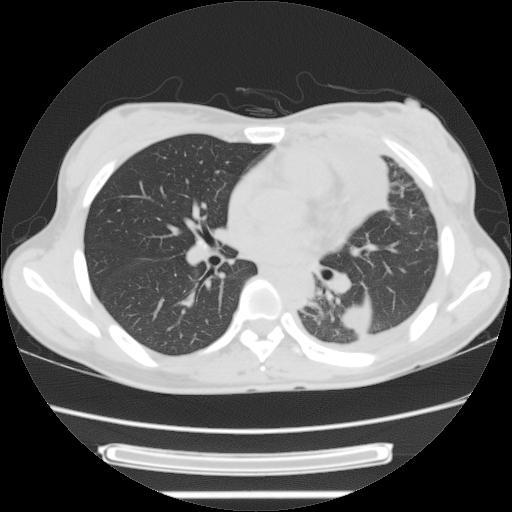

女,29岁,胸部不适,在外院胸片提示胸腔积液,到我院ct检查。

肺窗:

1、左侧包裹性积液伴叶间积液 2、右肺多发结节考虑增殖结节

左肺上叶不张,左侧胸水,叶间裂积液,纵隔淋巴结,脾脏钙化,考虑左肺上叶支气管内膜结核,结核性胸膜炎,脾结核

考虑:1.两肺tb;2.左侧胸膜炎、胸腔积液。

考虑两肺结核,左侧包裹性积液,叶间积液。

右肺多发结节。左胸腔多发包裹性积液。